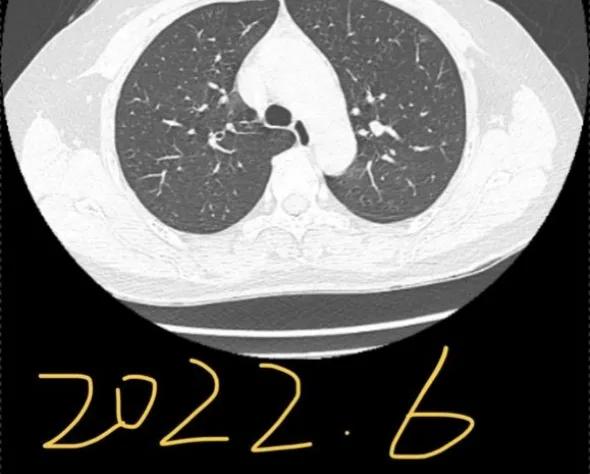

一个安徽的宝妈,在6月的时候向我求助:她的妈妈CT查出了两处磨玻璃结节,尺寸都在6-7mm。后来随访过程中发现一个结节增长到了10mm,并且出现了侵犯胸膜的情况,加上省会医生给的一个“微浸润”,这下让这位宝妈异常焦急。再次向我求助,想来重庆新桥进行手术。(插一句,我对宝妈这样质实的孝,异常钦佩;对于宝妈的要求,我一定是安排好所有的绿色通道,亲自处理的)。手术很成功,虽然难度极大(全胸腔粘连),但是考虑到患者未来恢复,和你需要照顾孩子的实际情况,我还是坚持全程微创,没有开胸。手术即治愈,未来慢慢恢复即可,不用担心。

2021年12月,我母亲做CT查出左肺上下叶各有一磨玻璃结节,大小均为6-7mm,医生让3-6月复查。今年6月复查,报告显示有一个侵犯胸膜,大小长至10mm。医生看影像后初判微浸润,让手术切除。慕名而来,恳请戴主任帮忙看看,我们好心安。

大的结节早期浸润性腺癌,小的结节原位或良性的。楔形切除小手术即可搞定。4mm的可以不切